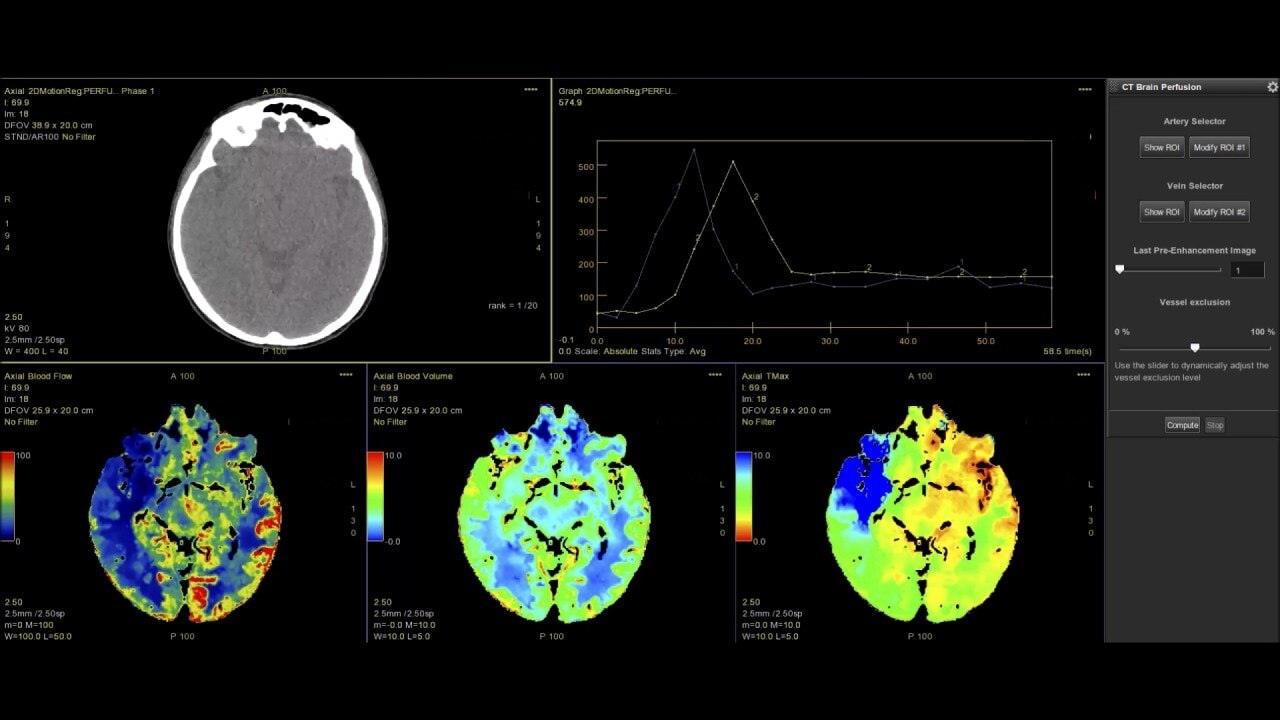

Myocardial perfusion

Complete guided workflow for assessing dynamic CT myocardial perfusion

The dynamic myocardial perfusion protocol is laid out in a series of three easy to follow steps. Start by selecting the series that has been generated from the non-rigid registration protocol and then follow the guided workflow: